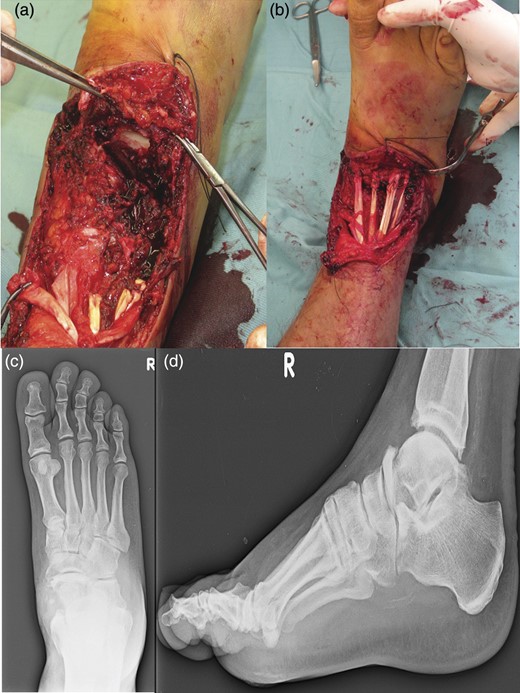

The medial approach was through a longitudinal incision, starting at the tip of the medial malleolus and carried distally 1 cm past the naviculocuneiform joint. The incision was deepened through the capsular tissues. The capsule and spring ligament were stripped from the navicular (Fig. 3).

Lateral approach at the base of the fourth metatarsal, and extended proximally toward the tip of the fibula, ∼1 cm short of the tip to identify the calcaneocuboid joint (a). Medial approach through a longitudinal incision, starting at the tip of the medial malleolus and carried distally 1 cm past the naviculocuneiform joint. It is evident of the antibiotic-loaded cement spacer. (b). An elevator was passed over the dorsal aspect of the talonavicular joint. The antibiotic-loaded cement spacer was removed (c).

An elevator was passed over the dorsal aspect of the talonavicular joint, completely freeing the joint. It was removed the antibiotic-loaded cement spacer.